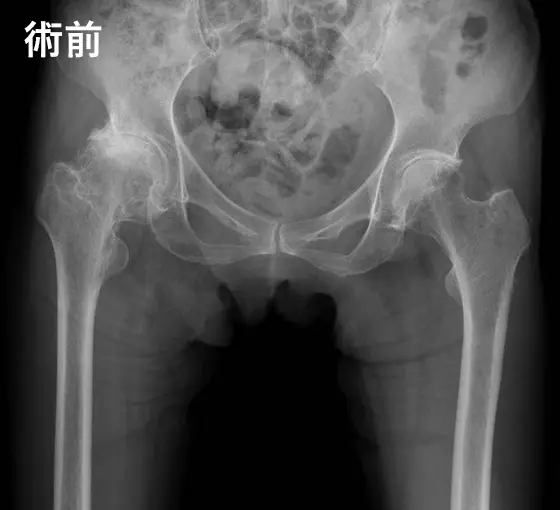

人工股関節手術の例

人工股関節手術の例:術前

変形性股関節症

人工股関節手術の例:術後